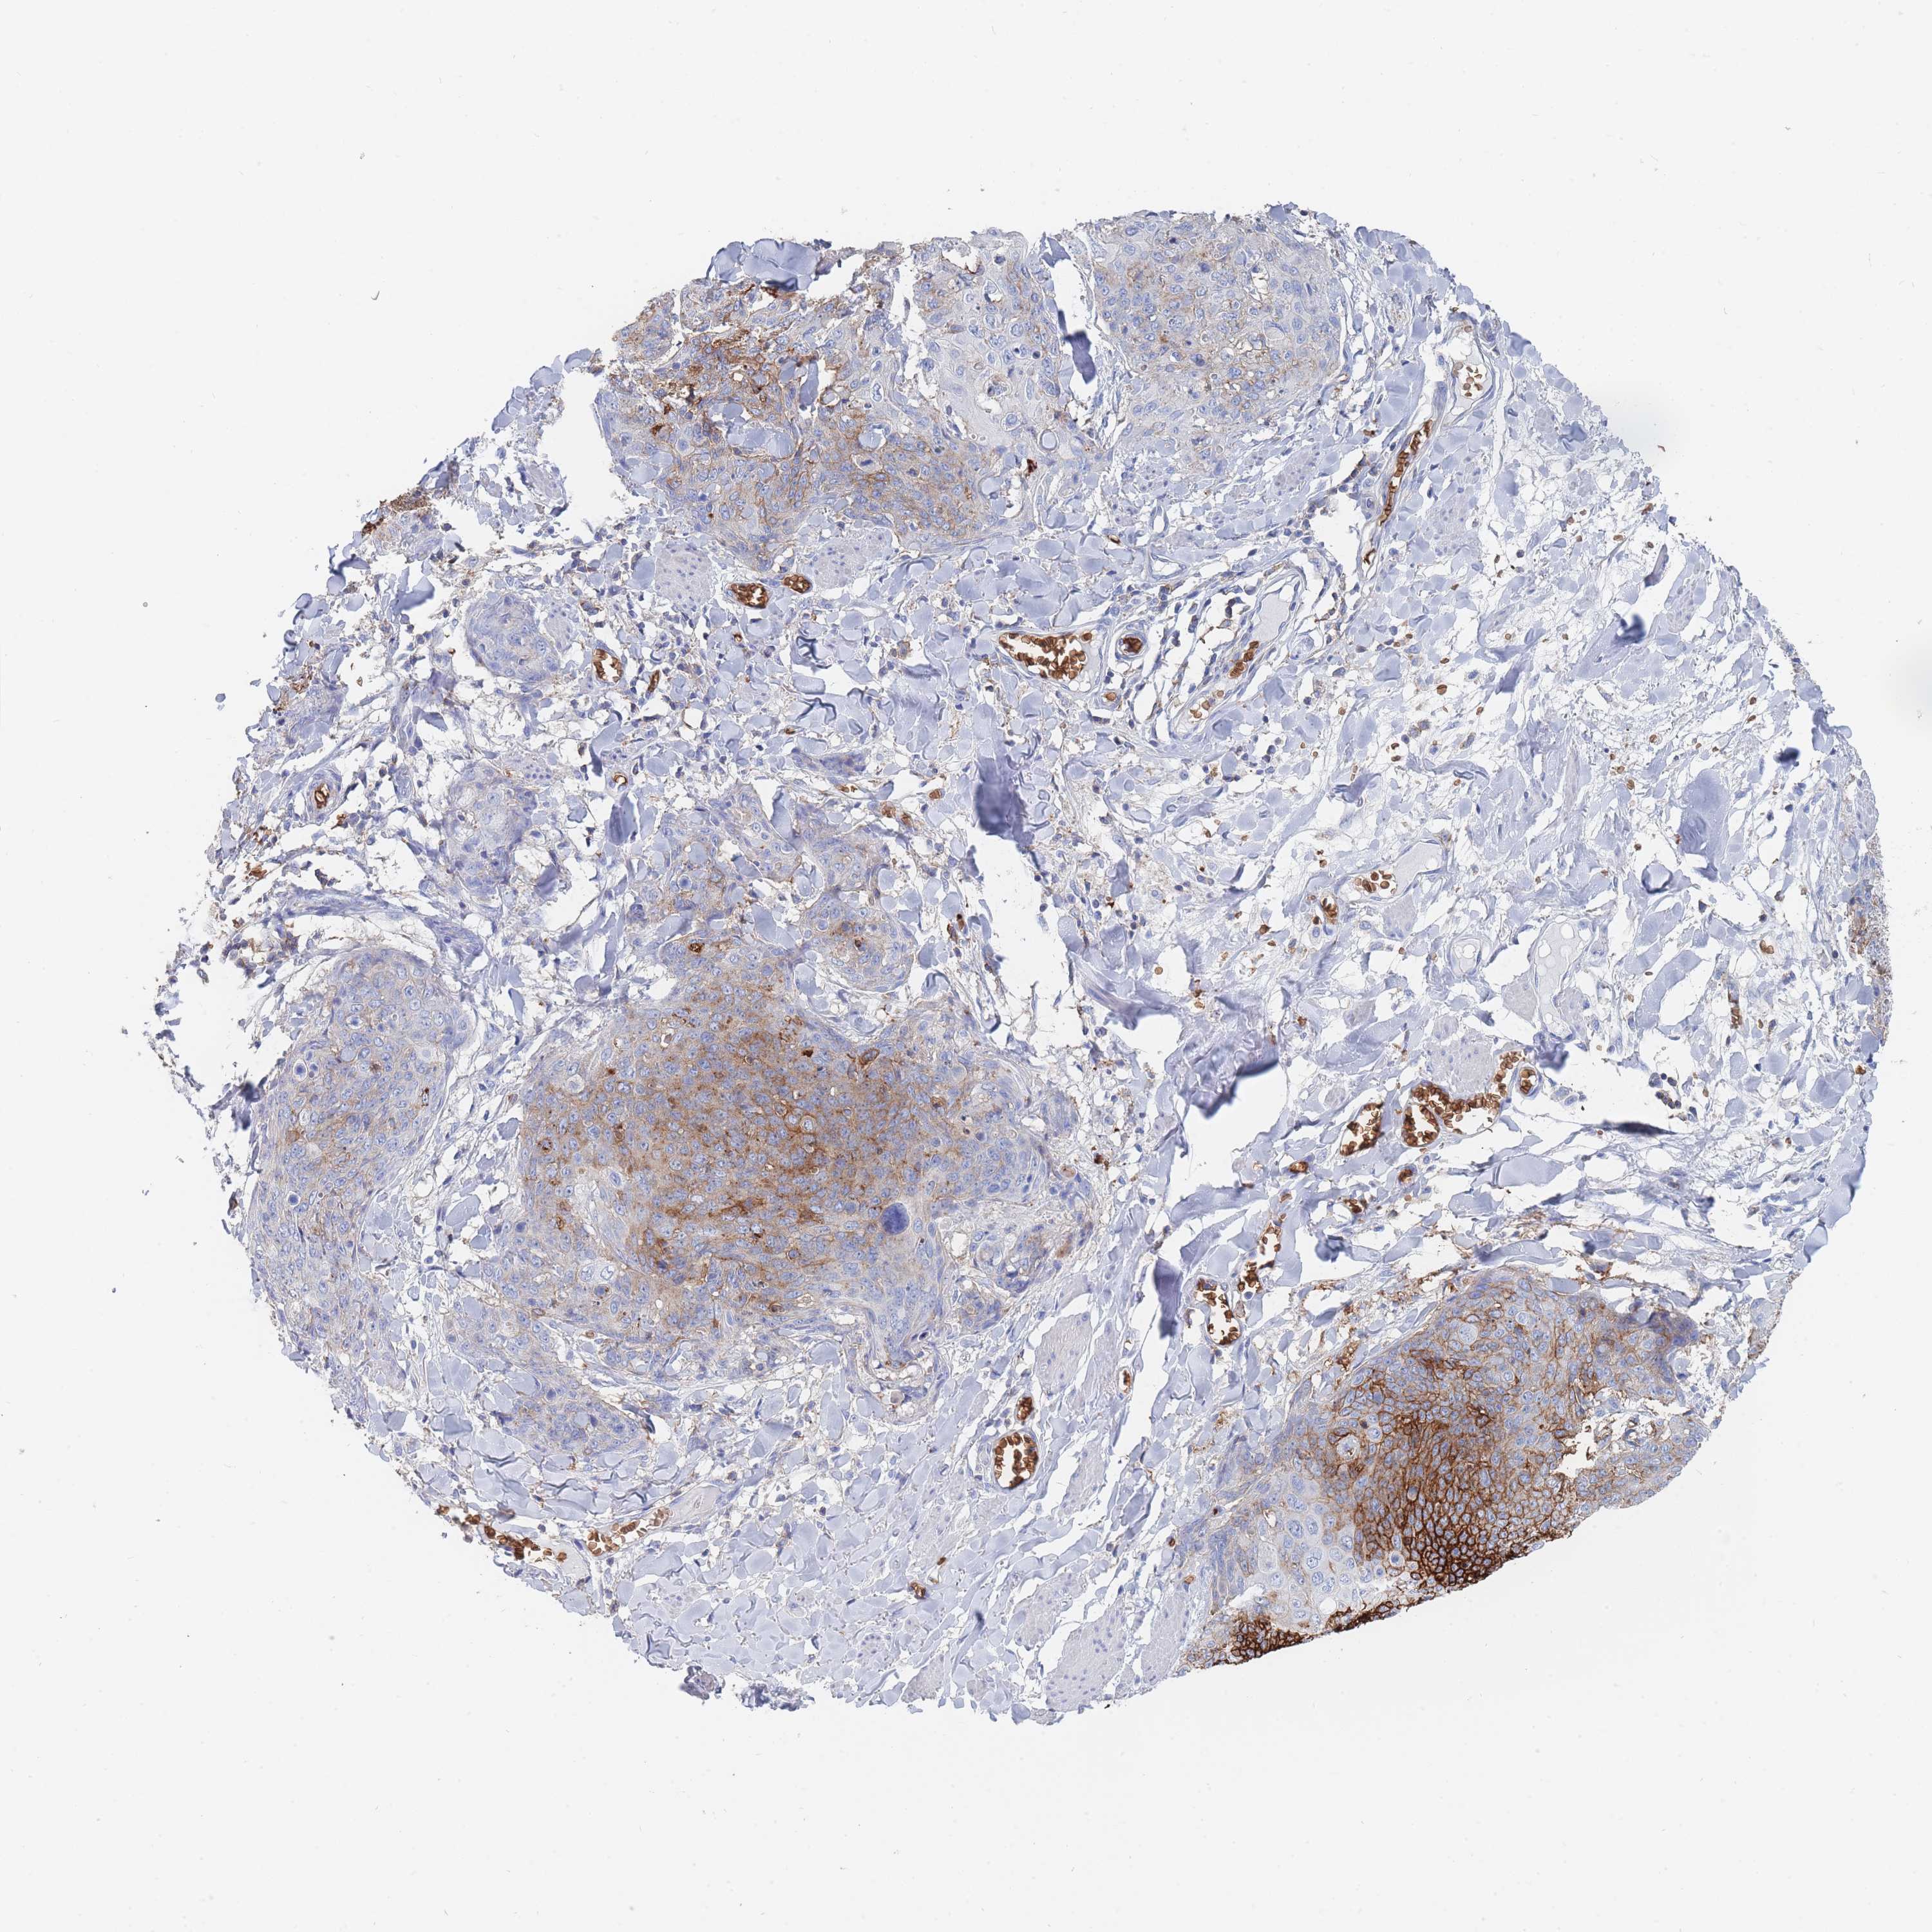

SKIN CANCER - Protein expressioni

A mouse-over function shows sample information and annotation data. Click on an image to view it in a full screen mode. Samples can be filtered based on level of antibody staining by selecting one or several of the following categories: high, medium, low and not detected. The assay and annotation is described here.

Each image is clickable and will lead to virtual microscopy that enables deeper exploration of all samples and also displays staining intensity scores, fraction scores and subcellular localization as well as patient and tissue information for each sample.

Antibody HPA031345

Antibody HPA058494

Antibody CAB002759

Squamous cell carcinoma, NOS